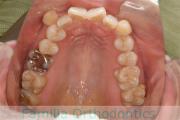

No.22V-296

- 叢生

- 上顎前突

- 19歳

- 女性

- 844

- 8448

- FEA

- 88万円

上の出っ歯を治したいとのことで来院されました。下あごの後退が強く、奥歯のすれ違いもありました。上顎のみ左右小臼歯を、親知らずは全て抜歯して、マルチブラケット法を行いました。2年半、30回程度の通院が必要でした。

上野前歯の移動量が大きく、この部位の歯根吸収のリスクが高いケースでした。